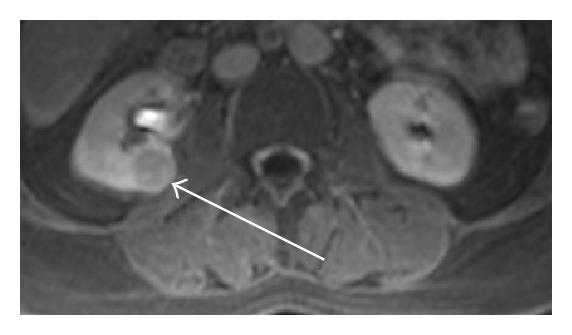

In the general population, renal cysts are the most common space-occupying lesions in the kidney. With this technique, 80% of detected renal masses are characterized as simple cysts [9] thus ending their diagnostic evaluation. The remaining 20% of renal masses require further study with CT or MR imaging [10]. Any mass detected that does not meet the strict sonographic criteria for a simple cyst should be further evaluated with CT or MR imaging of the kidneys. However, one or two thin septations may also be visible sonographically in simple renal cysts [11]. Because these findings are diagnostic, no further imaging or followup is needed in the evaluation of these lesions. However, other atypical features sonographically detected calcifications; more than two septations, septal thickening or nodularity, and the presence of solid components indicate that sonography alone will not be adequate for complete evaluation of these renal masses (see Figure 2). The addition of Doppler sonography, color Doppler sonography, power Doppler sonography [12, 13], and sonographic contrast agents may further improve the detection and characterization of renal masses. However, none of these techniques preclude the need for CT or MR imaging of renal masses that do not meet the sonographic criteria for diagnosis of a simple cyst.